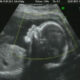

Ecografia fetale 16 sett. con sequenza in 4D